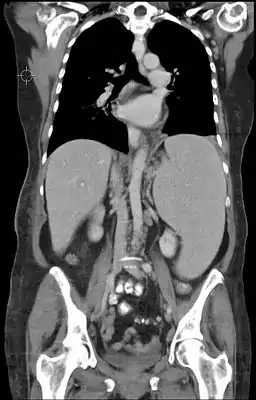

Гепатоспленомегалия (лат. Hepatosplenomegaly) — синдром, характеризующийся одновременным увеличением селезёнки и печени[1]. Диагностируется методами пальпации и перкуссии, а также при ультразвуковом или КТ-исследовании. Визуально при данном синдроме в области правого подреберья может наблюдаться выбухание, смещающееся при вдохе, обусловленное увеличенной печенью.

Основная особенность гепатоспленомегалии — это признаки начинающегося гиперспленизма: тромбоцитопения, эритроцитопения, лейкопения, обнаруживающиеся в клиническом анализе крови[2].